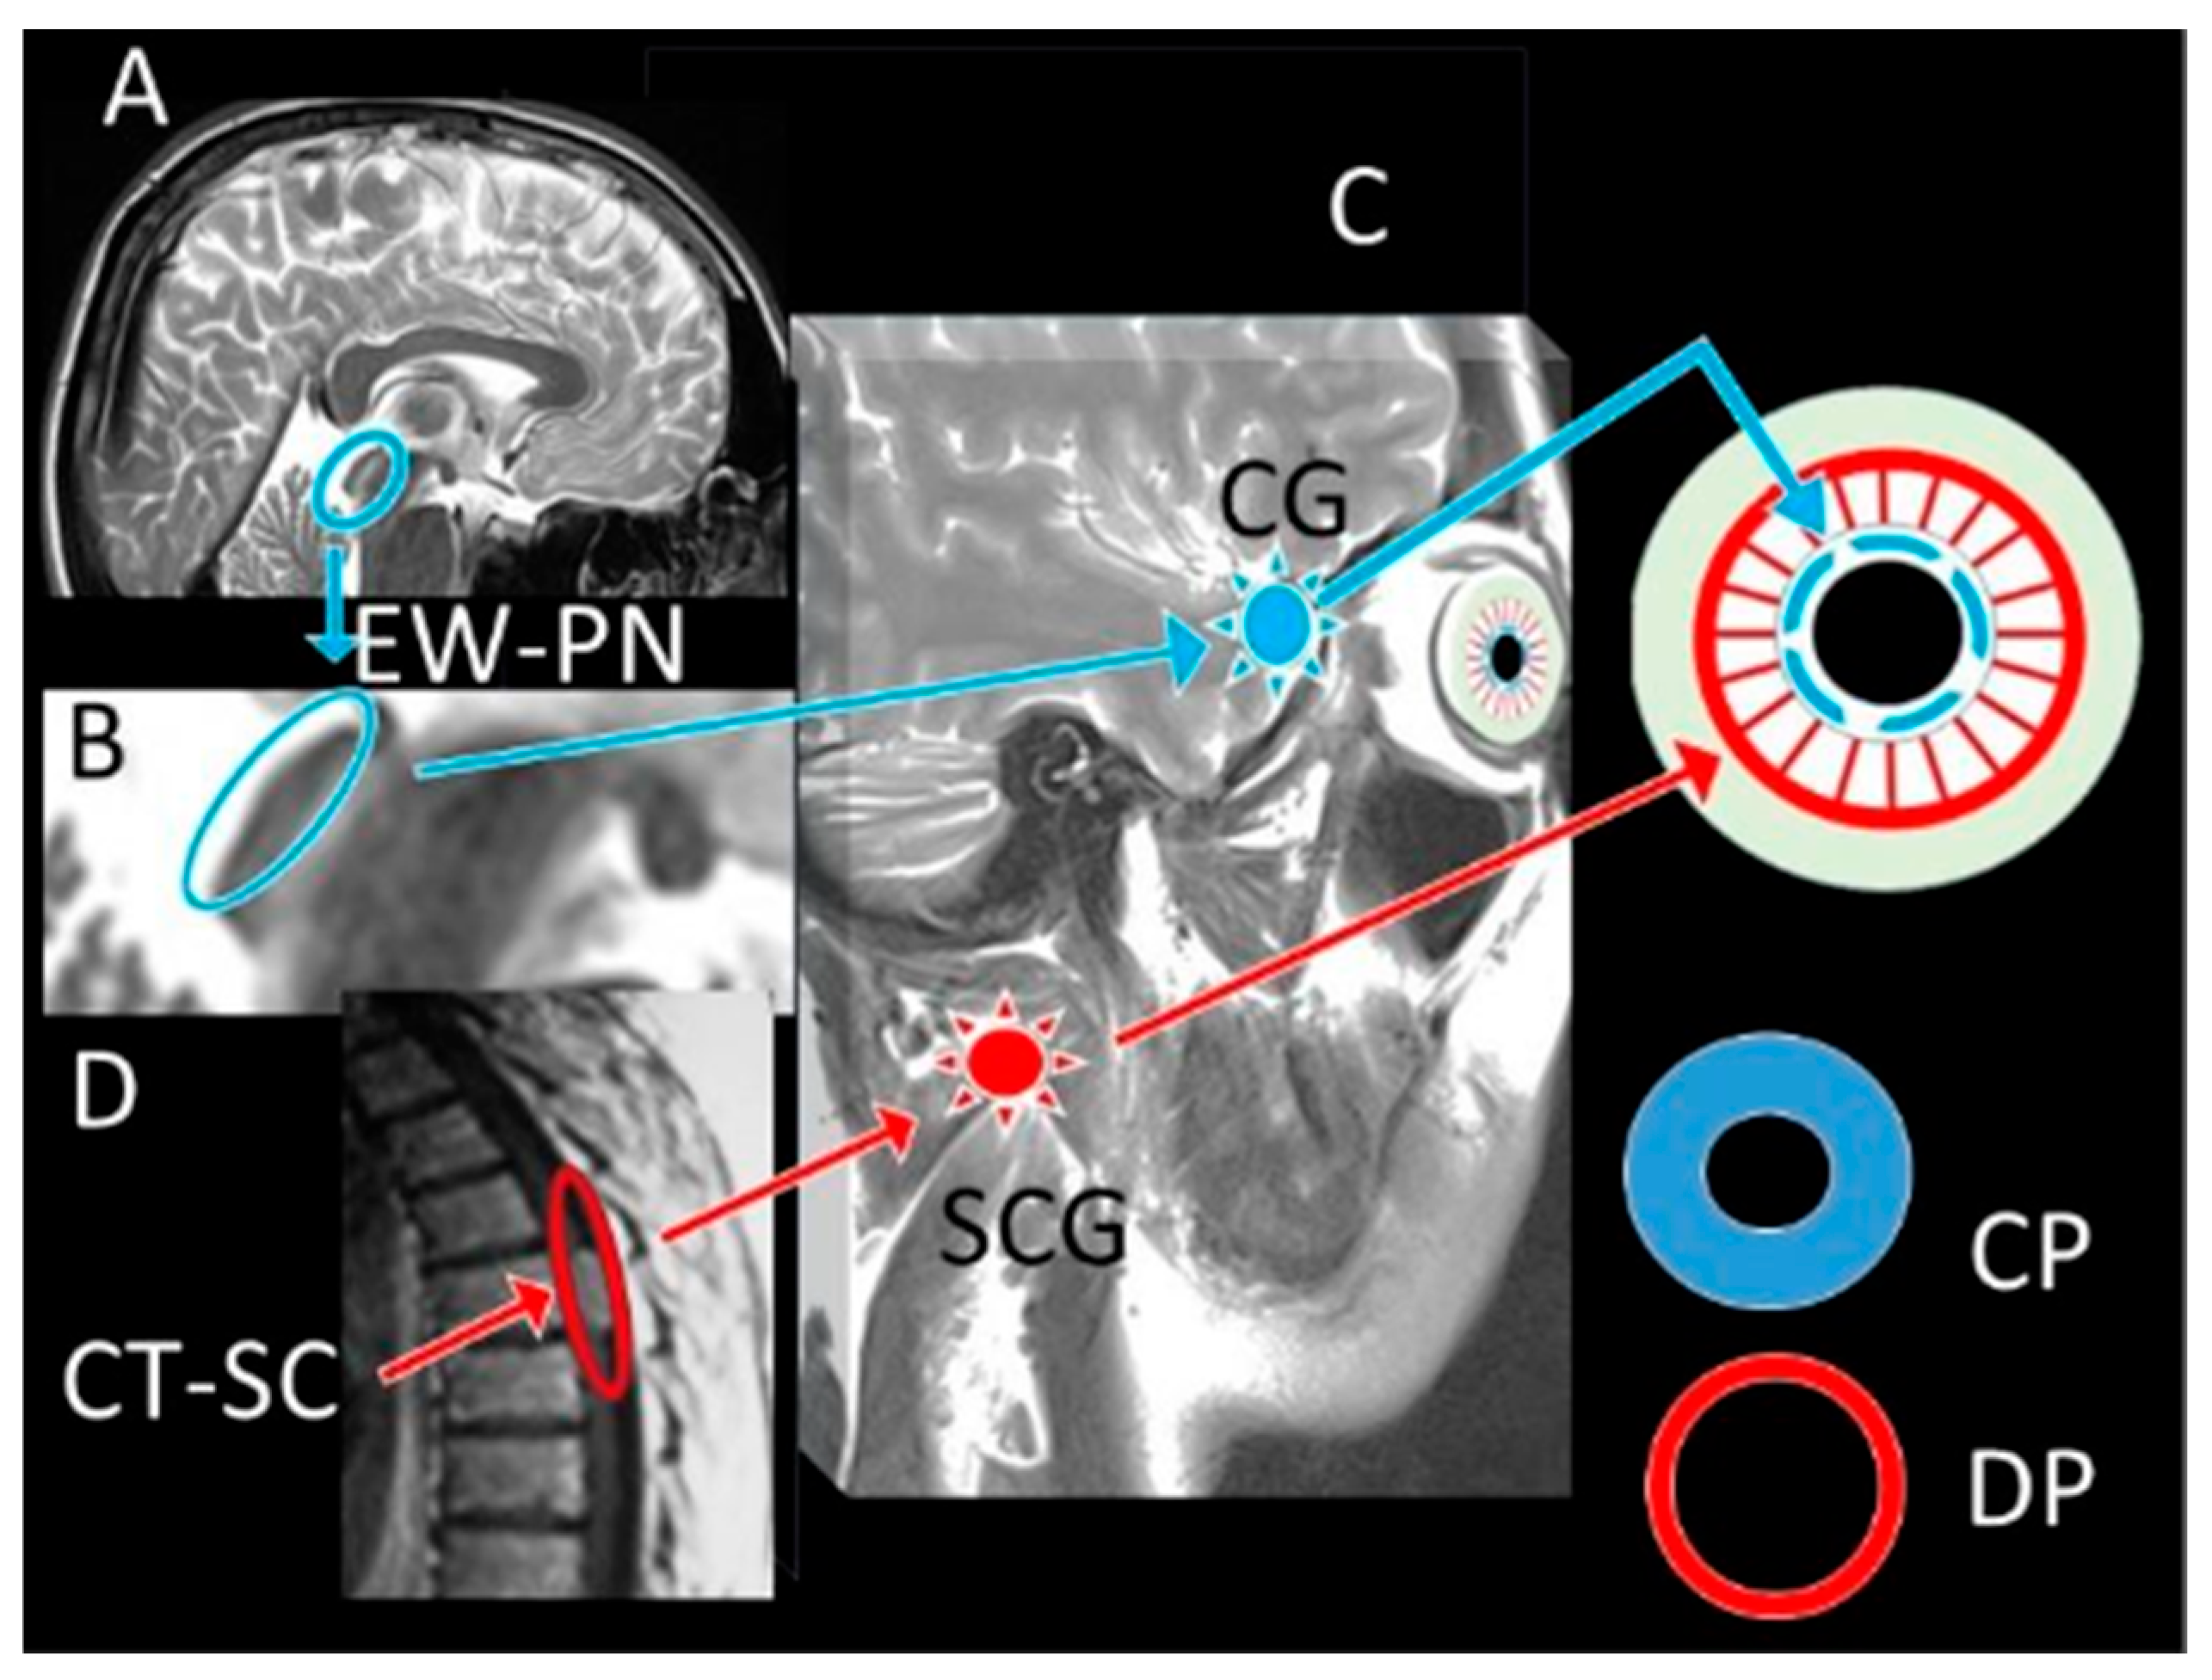

These results have far-reaching clinical consequences. In critical care environments, current neurological assessment techniques depend mostly on qualitative or semi-quantitative pupil assessments vulnerable to significant interobserver variation [55,56]. A standardised, ratio-based measure like the DADA Index will greatly increase the correctness and consistency of pupillary evaluation across many different clinical environments. İn the studies conducted [16,25,57] found that even small increases in the accuracy of neurological evaluation could lead to notable changes in clinical results by means of early intervention and more suitable treatment techniques. Building on this potential, the DADA Index has possible benefits in both initial assessment and continuous monitoring in the particular setting of subarachnoid haemorrhage, when fast and precise neurological assessment is critical. Early identification of neurological degeneration following SAH has been shown to greatly enhance results, especially when intervention takes place before permanent damage. Unlike traditional pupillary evaluation, the DADA Index could offer a more sensitive early warning system that might enable earlier identification of rising intracranial pressure, imminent herniation, or progressive brainstem compression. Moreover, the DADA Index could be used for other acute neurological disorders outside SAH. Boulter and et al. [58] research on pupillary alterations in traumatic brain injury indicates that more complex pupillary measurements may increase predictive accuracy. Feng and et al. [59] likewise showed that in post-cardiac arrest patients with hypoxic–ischemic encephalopathy, quantitative pupillary evaluation enhances outcome prediction. By offering a more physiologically based measure that considers individual differences in eye anatomy, the DADA Index might improve these evaluations. Further extending its implications, our results imply, perhaps most importantly, that the DADA Index could be a useful complement to present brain death criteria. Though present techniques lack consistency and are influenced by other variables, pupillary evaluation stays a foundation of the clinical examination, as Wijdicks and et al. [60] point out in their thorough study of brain death diagnosis. By measuring the correlation between iris and pupil surface areas, the DADA Index could offer a more consistent and objective sign of total parasympathetic pathway failure, hence lowering doubt in these vital decisions. Furthermore, beyond the identification of parasympathetic failure, the potential of the DADA Index extends to its critical role in the differential diagnosis of pathologies involving isolated or combined sympathetic and parasympathetic system damage. The DADA-I’s primary strength lies in this differential diagnosis. Circulatory disturbances affecting the oculomotor complex and EWN (e.g., midbrain ischemia) lead to parasympathetic failure and pupillary dilation, causing the DADA-I value to decrease. Conversely, pathologies of the cervicothoracic spinal cord, which lead to sympathetic failure, result in unopposed parasympathetic dominance and excessive miosis, causing the DADA-I value to increase. While the literature focuses on ‘brain death,’ it often neglects ‘spinal cord death’ and the concept of ‘cerebrospinal death.’ Whereas pupil diameter alone can be misleading, DADA-I accounts for both the iris (sympathetic) and pupil (parasympathetic) areas. It thus offers a more reliable tool for understanding the pathology in craniospinal trauma patients: a decrease in DADA-I suggests cranial pathology, while an increase suggests spinal pathology (Figure 4). This is in line with Lenga and colleagues’ [61,62] recent work advocating for more exact physiological measures in brain death diagnosis. Building on this standardisation potential, in addition to these insights, this study’s findings suggest that the DADA Index could serve as a valuable tool in standardising pupillary assessments across different practitioners and institutions.

Figure 4.

Table of Pathogenesis: Pathogenesis Table: Human brain MRI; the location of the Edinger Westphal and Perlia nuclei (EW-P) located in the tegmentum mesencephali in the superior colliculus (A,B), their connection with the ciliary ganglion network (CG) and pupillary muscles (Blue arrows), the location of the parasympathetic pupilloconstrictor fibres and muscles affecting the pupilloconstrictor muscles that innervate the pupillae (Blue/(A,B)) (C); the postganglionic fibres going to the pupillodilator muscles (Red arrow/(B)) of the sympathetic cervical ganglion network (SCG) originating from the cervicothoracic sympathetic centre (CT-SC) and coming to the superior cervical sympathetic ganglion (SCG), and the pupillodilator muscles they affect are observed (D). While the pupils contract with the parasympathetic effect (CP), they dilate with the sympathetic effect (DP). Representative constricted pupil (Blue Ring) and dilated pupil (Red Ring) are seen.